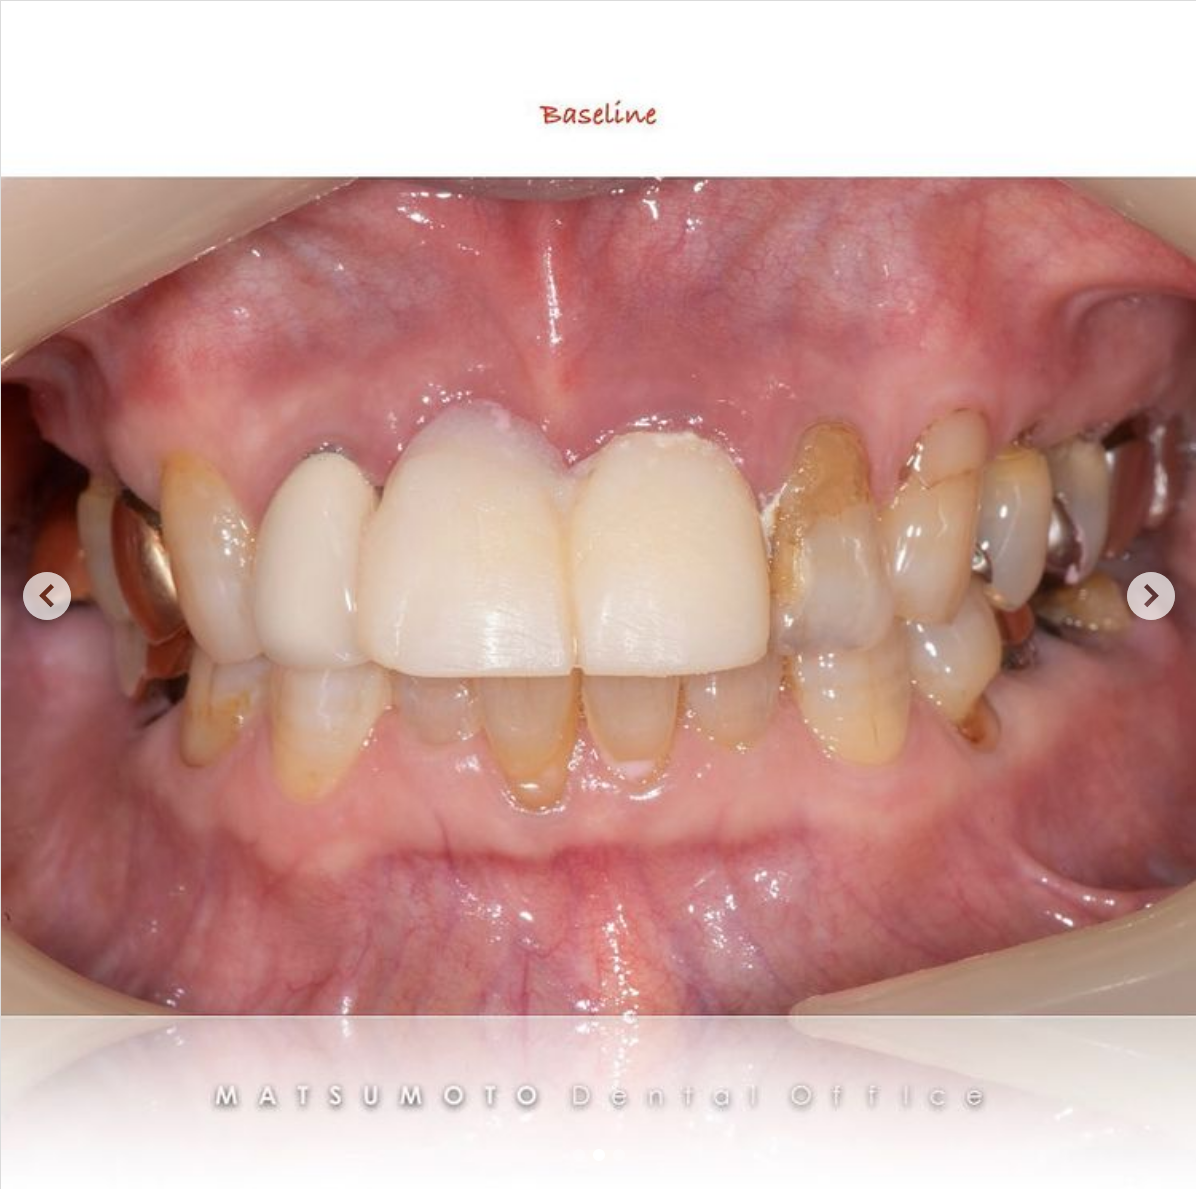

症例紹介28:オールオンシックス(All-on-6)インプラント治療《60代女性》

患者情報:60代女性

治療内容:現在他院で右上の根の治療をしているが、全体的に噛めないので治療を希望され来院。

術前の診査診断

術前写真

上顎:虫歯がひどく、保存不可能な状態である。

下顎:インプラントが入っているが、被せ物がなずれたまま放置になっている。

パノラマX線

上顎:根の病気と虫歯で保存不可のな状態。

下顎:インプラントが不適切な位置に入っており、撤去が必要な状態。

オールオンシックス(All-on-6)インプラント治療を終えて

最終補綴

上顎:両側サイナスリフト後のロケーターアバットメントによる金属床ブリッジ

下顎:All-on-6によるフルジルコニアブリッジ

治療のリスクと副作用

治療期間:約1年半

治療費:¥6,200,000(税込)

リスク:上顎のロケーターアバットは定期的に交換が必要です。また、上顎の人工歯が減ってきますので、定期的なメンテナンスが重要です。